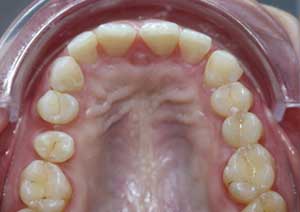

Après